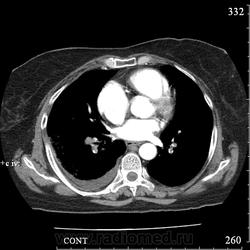

Еще один случай диагностики ТЭЛА методом КТ-ангиографии у женщины 59 лет. Основная клиническая жалоба - выраженная одышка. Определяется: полный дефект наполнения в системе правой ЛА (бифукация и нижнедолевая), неполный дефект наполнения в левой ЛА (нижнедолевая), пристеночные тромбы по задней стенке в области бифуркации обеих легочных артерий. Инфаркт (массивное кровоизлияние) нижней доли правого легкого. Правосторонний малый (120см3) гидроторакс. Несмотря на выраженные тромбы, поперечники легочных артерий - в пределах нормы.; на нативной (безконтрастной) КТ - тромбы не видны. Несмотря на почти полный дефект наполнения в левой нижнедолевой артерии, изменений в легочной ткани левого легкого нет. Также приводится топограмма, как вариант, приближенный к рутинной рентгенограмме